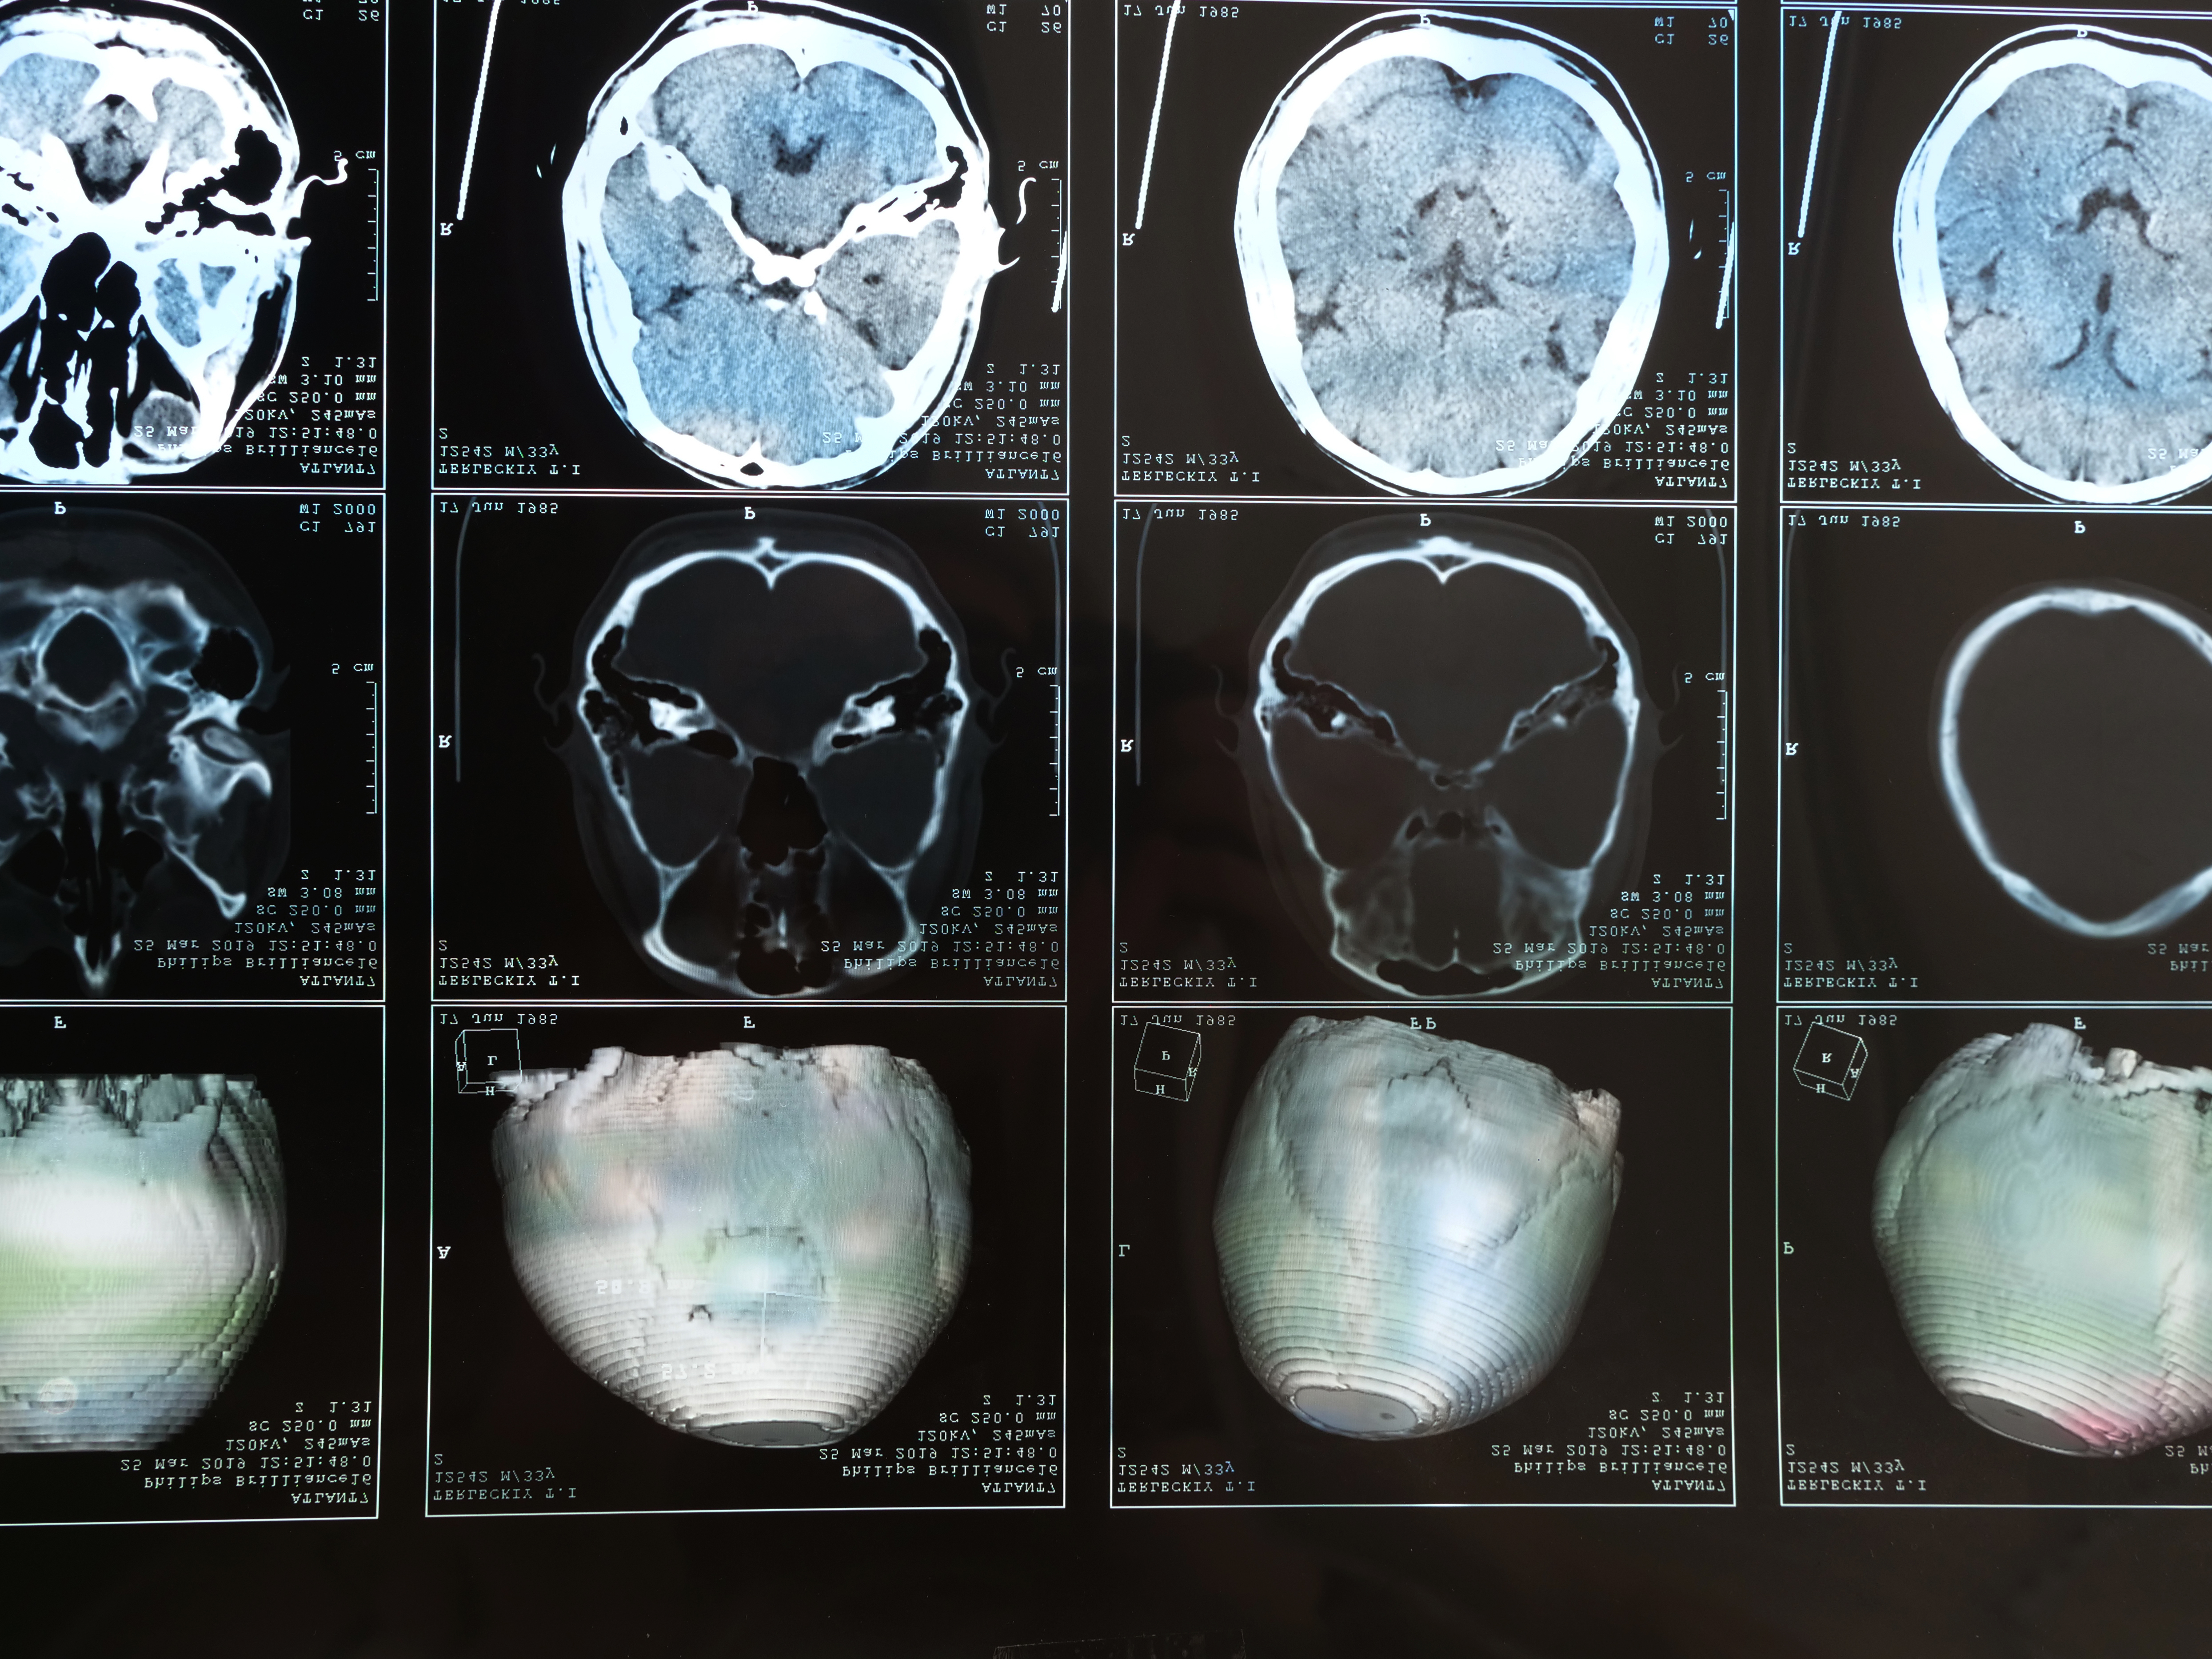

Gathering Medical and Legal Evidence

The foundation of any strong TBI case is solid evidence. We gather detailed medical records, brain scans, and diagnostic reports that clearly document your injury and connect it to the accident that caused it. We also secure witness statements, police reports, and accident scene documentation to establish exactly how negligence occurred.Â

Are TBIs always visible on scans like MRIs or CTs?

Not always. Mild TBIs or concussions may not appear on imaging, even though they cause significant cognitive, emotional, or physical symptoms. Medical documentation and evaluations are critical in these cases.